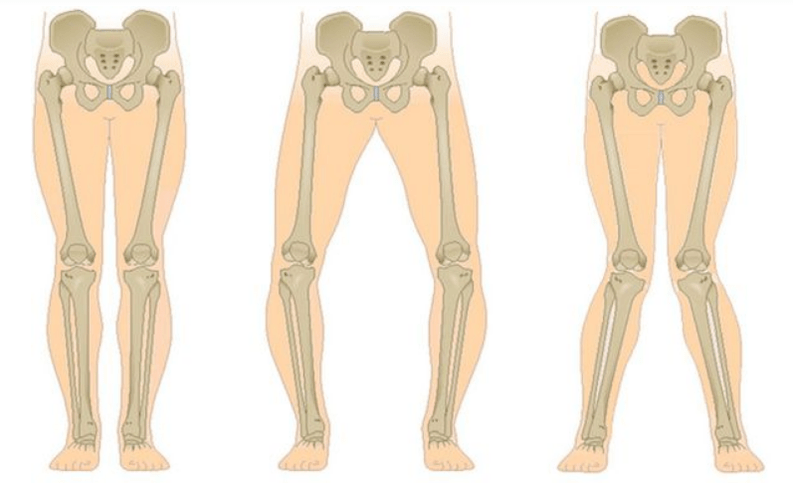

The last stage of gonarthrosis is distinguished by the fact that the pain becomes almost constant, causing anxiety not only when walking, but also at rest, even at night, when patients have to look for a comfortable position to sleep.Movement is more limited: it is difficult to fully bend and straighten the leg.The joint deforms and increases in volume.A valgus (X-shaped) or varus (O-shaped) foot deformity is often observed.The gait becomes unsteady and jerky.In severe cases, a cane or crutches are needed.

In arthrosis (osteoarthrosis), in addition to the progressive destruction of cartilage, the loss of its elasticity and shock-absorbing properties, the bones are gradually involved in the process.When loaded, sharp edges (exostoses) appear, which are mistakenly considered "salt deposits" - in classic arthrosis, salt deposits do not occur.As arthrosis progresses, it continues to "eat" the cartilage.Then the bone is deformed, cysts form there, all the structures of the joint are affected and the leg bends.

Depending on the number of affected joints, unilateral and bilateral gonarthrosis are distinguished.